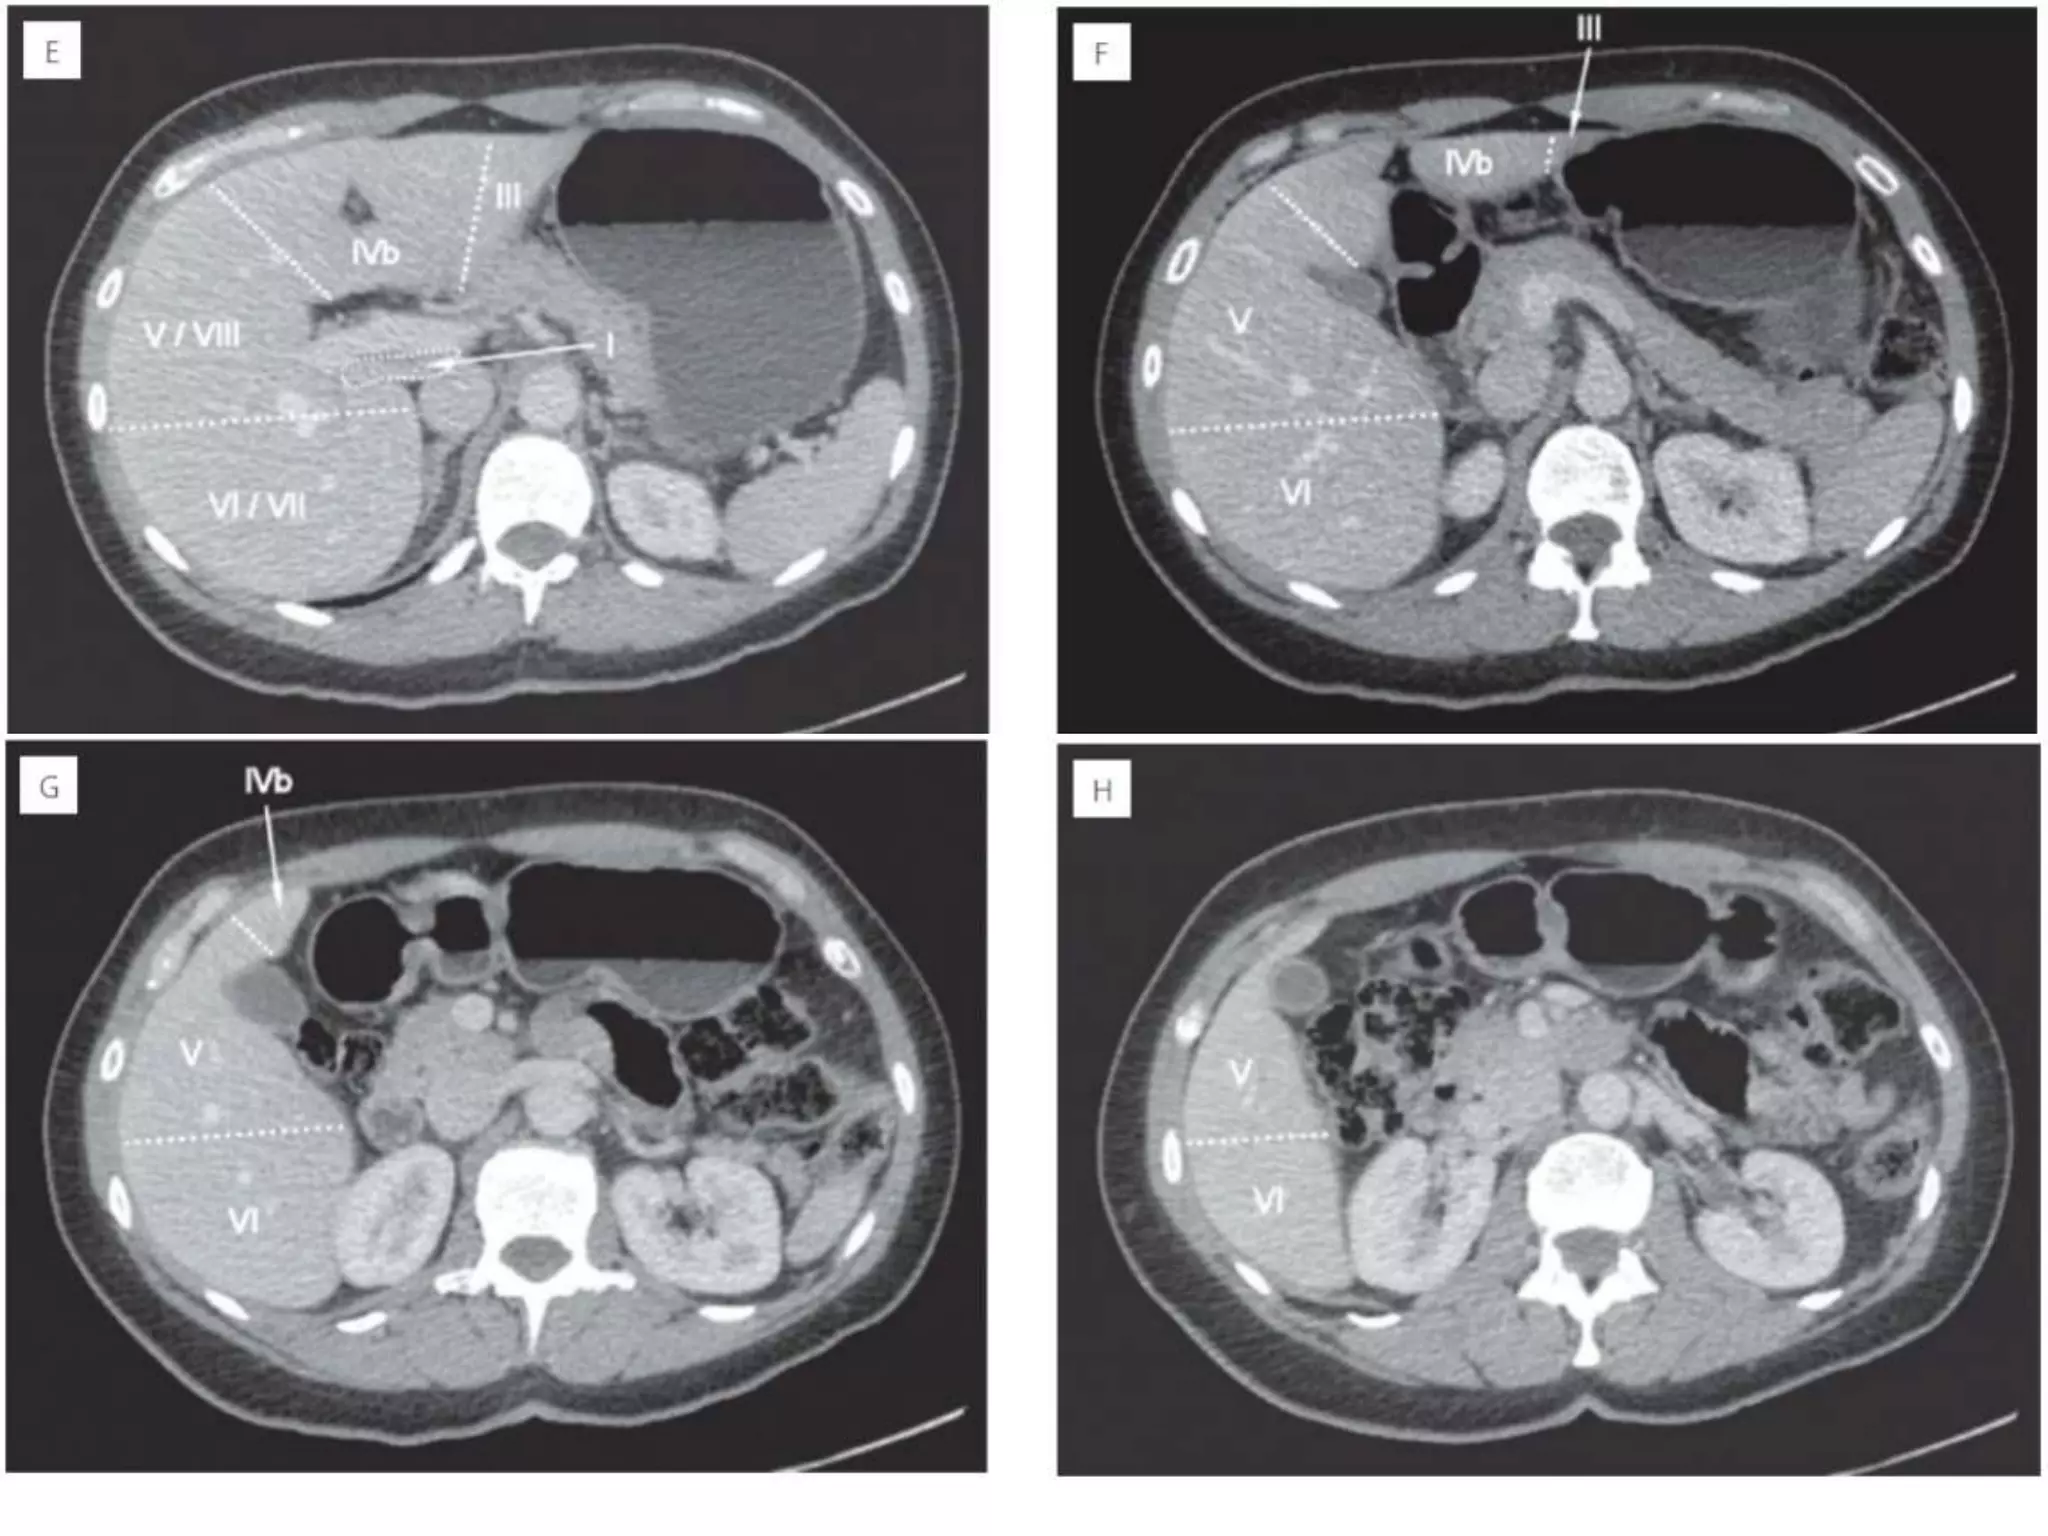

• 23.

How to separateliver segments on cross sectional imaging Left lobe: lateral(II/III) vs medial segment (IVA/B) Extrapolate a line along the falciform ligament superiorly to the confluence of the left and middle hepatic veins at the IVC (blue line). Left vs Right lobe: IVA/B vs V/VIII Extrapolate a line from the gallbladder fossa superiorly along the middle hepatic vein to the IVC (red line). Right lobe: anterior (V/VIII) vs posterior segment (VI/VII) Extrapolate a line along the right hepatic vein from the IVC inferiorly to the lateral liver margin (green line).